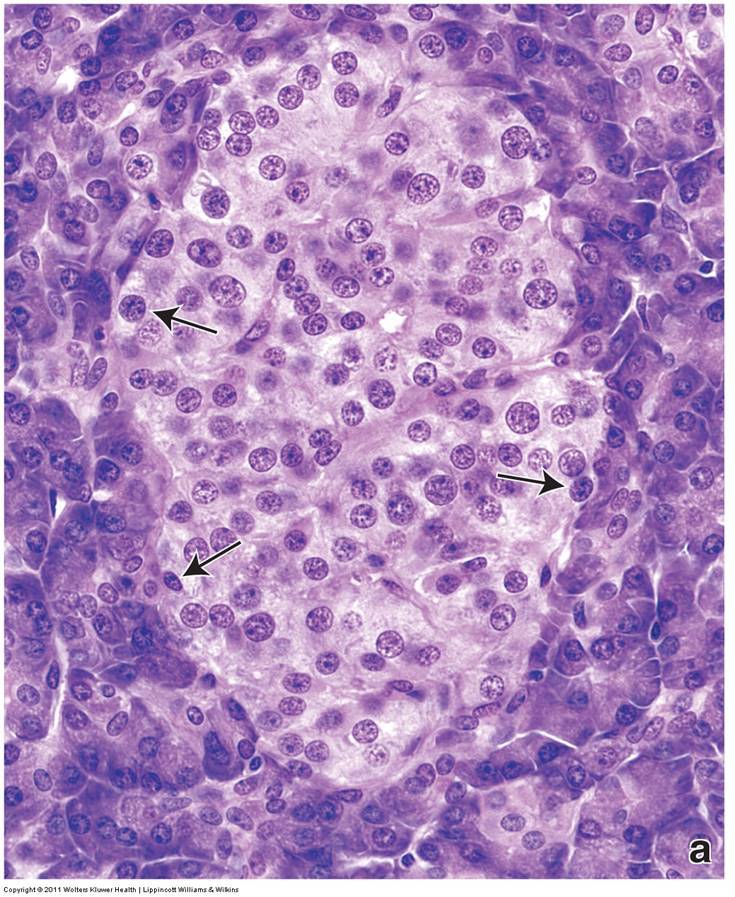

What are three cell types present in the light zone?

Alpha cells at the periphery

Beta cells at the core of the islet

Delta cells at the periphery